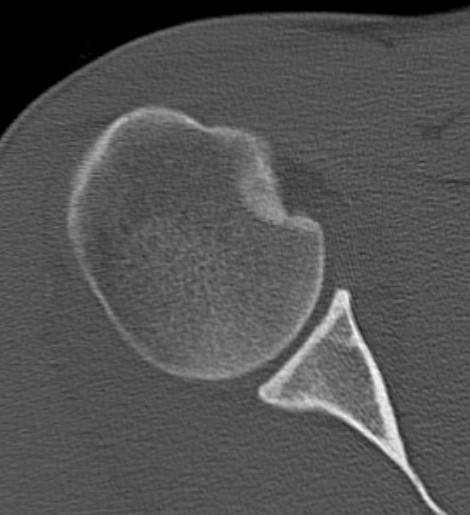

CT scan

Confirms dislocation

Reverse Hill Sachs

Humeral head defect

- caused by impaction of anterior humeral head on posterior glenoid

- intra-articular

- measured as a percentage of the articular surface

Lesser tuberosity fractures

Posterior glenoid fractures / bony bankart